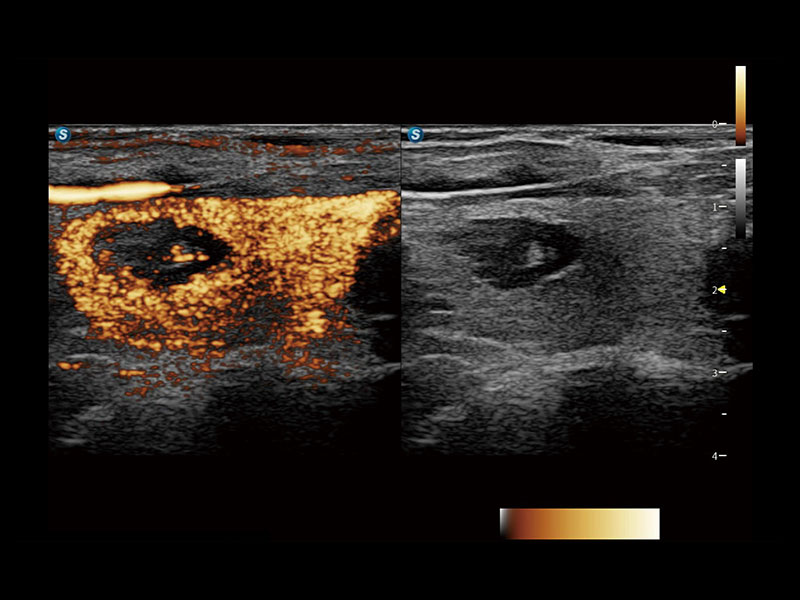

便携式彩色多普勒超声诊断系统

作为开立医疗全新打造的高端全域笔记本超声,X11集成了当前先进的硬件架构和精密的设计工艺,提升多科室临床医生在常规影像检查中的诊断能力,为临床提供全面的诊疗支持。